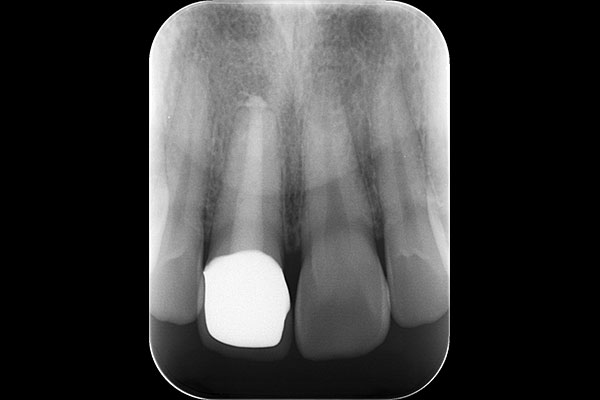

2.治療前のレントゲン

レントゲンで撮影すると、根の先に黒い影あり、膿が溜まっている様子がわかります(黄色い矢印)。

歯と冠の間にある隙間から入ったばい菌が、歯の中で増えて根の先に出ていき炎症を起こしていることが原因です。